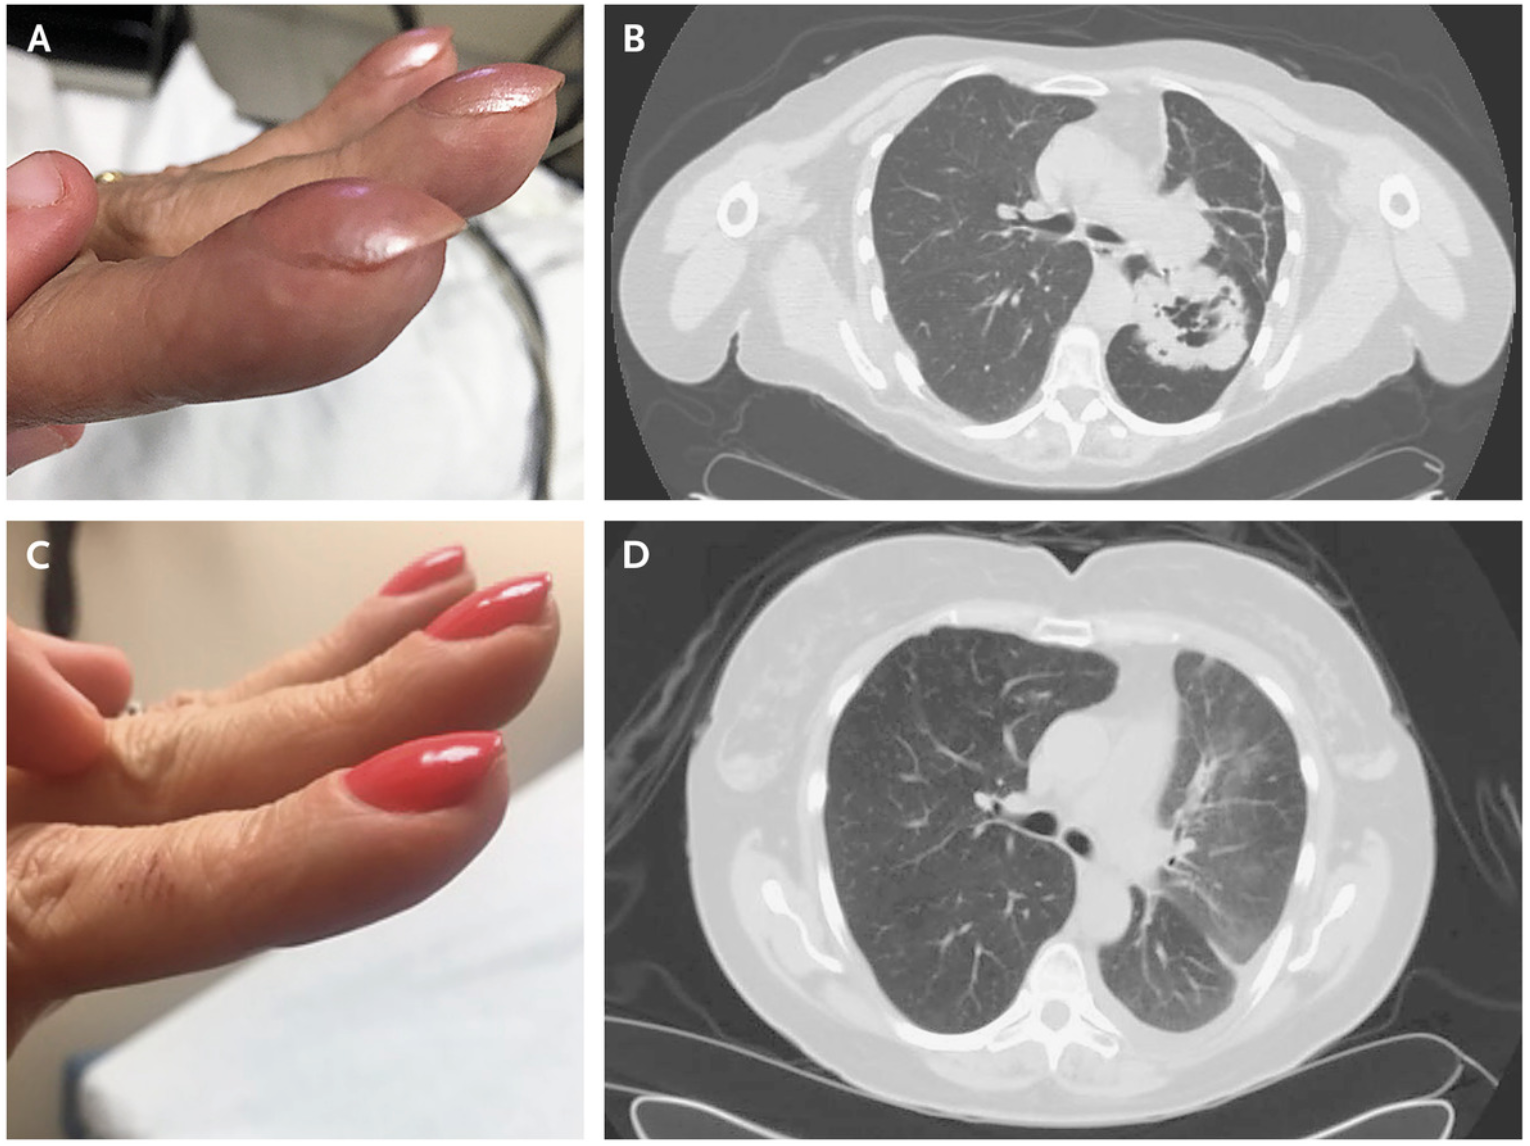

爪も大事な身体所見 Part④~ばち指~原因不明と戦う総合診療医ドクターP。

ばち状指を見たときに考えるべきことは? - 亀田メディカルセンター亀田総合病院 呼吸器内科 呼吸器道場。

ばち指の見分け方3選 画像付きで解説 原因疾患も併せて学べますコキュトレ。

ばち指で考える疾患は? : 今日なに読もう〜病院総合診療医の論文ブログ。